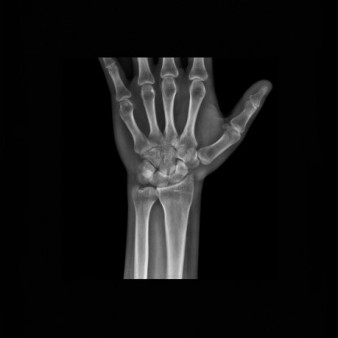

Перелом лучевой кости запястья — это распространенная травма, которая возникает преимущественно при падении на кисть . Подобные повреждения встречаются среди людей всех возрастов, сопровождаются болевым синдромом, отечностью, ограничением движений и . . .

Рентген лучезапястного сустава: что можно обнаружить на снимке? Когда может назначаться рентгенография кисти руки? В идеале рентгеновские снимки в нескольких проекциях должны отобразить все составляющие кости и суставы запястья и кисти: 3-гранная, полулунная . . .